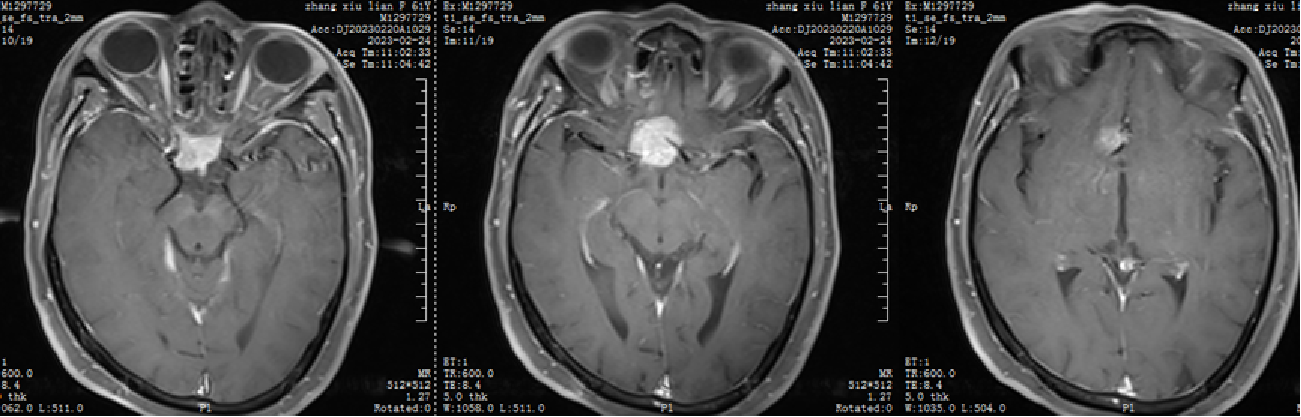

1.患者张XX,女,61岁,以“头晕2天”为主诉入院。

自近蝶窦前壁处向左侧推挤鼻中隔,离断筛骨垂直板,咬除部分近蝶窦处骨性鼻中隔,分离双侧鼻粘膜显露蝶窦前壁,自蝶窦开口上方做沿鼻中隔做粘膜瓣备用,末端到中鼻甲位置,将粘膜瓣压向下鼻道,高速磨钻磨除蝶窦下壁骨质,鞍结节骨质。术中视神经管清晰可见,给予保护,海绵间窦出血给予流体明胶+凝血酶止血;等离子刀一边止血一边切开硬脑膜见白色肿瘤质韧,边界清晰,大脑前动脉分支粘连于肿瘤表面,给予小心分离,以刮圈,咬切钳等小心清除肿瘤组织;内镜下将肿瘤完整切除;取右侧大腿皮下脂肪及阔筋膜备用,以人工硬膜修补和明胶海绵封闭鞍底硬膜,将脂肪放置于切口,并缝合于鞍底硬脑膜上固定铺平,阔筋膜覆盖于脂肪外边,蝶窦内充填明胶海绵止血,鼻粘膜瓣覆盖于蝶窦;碘仿纱条填塞鼻腔;护士清点棉条、器械、纱布无误,撤出鼻镜。

术后CT

本例患者术前做了充分的讨论和准备,术后恢复良好。